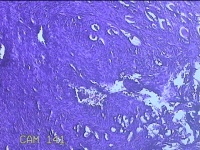

右侧前臂结节

性别

女

年龄

38岁

临床诊断

皮下结节

一般病史

发现右侧前臂结节1年余。

标本名称

大体所见

灰白粉红色带皮肤样组织0.8x0.7x0.3cm一块,表面带梭形皮肤0.8x0.7cm,皮下见结节0.8x0.5x0.3cm一个,切开结节呈实性,切面灰白粉红色,质软。